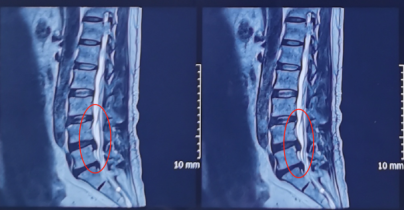

术前影像学资料